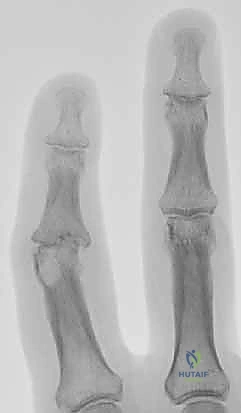

- Psoriatic arthritis can lead to remarkable bone loss, often presenting as "pencil-in-cup" deformities or the severe bone resorption characteristic of arthritis mutilans. Arthrodesis is often the most reliable method to halt this destructive process.

- In psoriatic arthritis, look for "pencil-in-cup" deformities or severe bone resorption (arthritis mutilans).